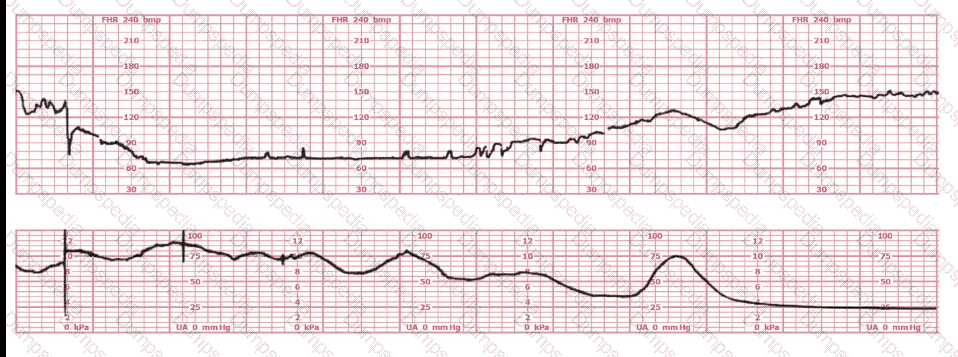

The decelerations seen in the fetal monitoring tracing shown are best described as:

The most probable underlying fetal physiologic cause for this tracing would be:

This is a tracing of a multiparous woman in the second stage of labor. The vertex is at +3 station. This pattern has continued for the last 20 minutes. She has been pushing for 2½ hours, and oxytocin is infusing at 12 milliunits/minute. Management should include